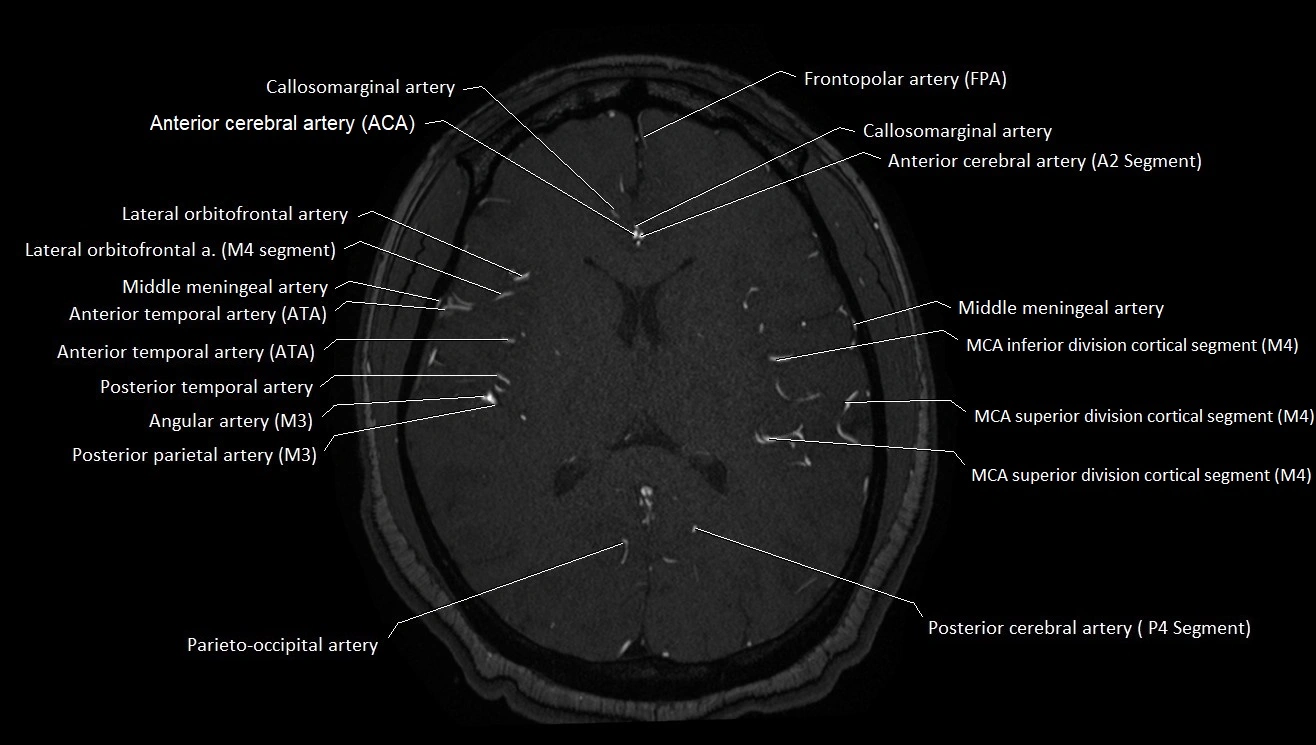

T1-weighted images:

• Vessel appears as a flow void (dark lumen) near the optic tract and temporal horn

• Surrounding parenchyma intermediate signal

T2-weighted images:

• Vessel lumen shows dark flow void

• Ischemic infarcts in its territory (internal capsule, thalamus) appear hyperintense

FLAIR:

• Vessel not seen directly; infarcts in AChA territory appear as hyperintense cortical/subcortical changes

• Chronic infarcts show gliotic hyperintensity

T1 Post-Gadolinium:

• Normal AChA enhances brightly and uniformly

• Abnormal focal enhancement indicates aneurysm, vasculitis, or AVM involvement